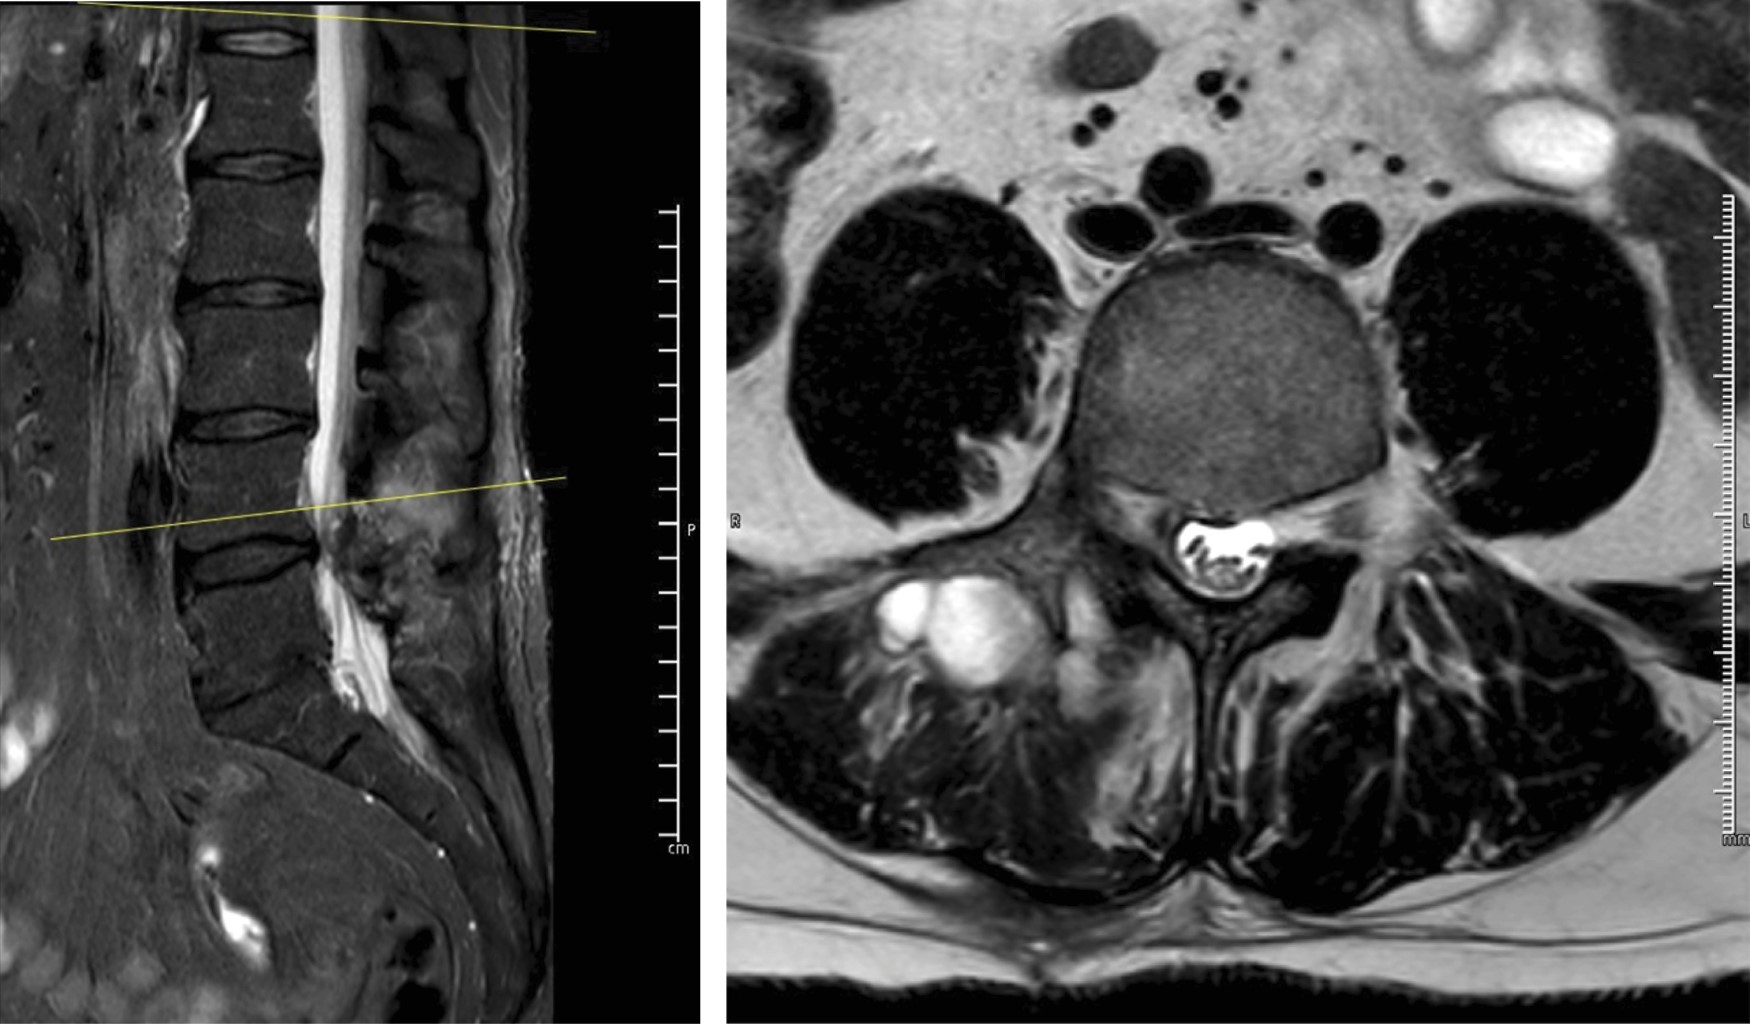

Se solicitó resonancia magnética simple de columna lumbosacra (Figuras 1 y 2), encontrando hernia discal extraforaminal L4-L5 derecha. Se decidió infiltración foraminal por la intensidad del dolor, sin embargo, no presentó mejoría, por lo que se decidió realizar microdiscectomía tubular tres días después. Se solicitaron estudios de laboratorio preoperatorios en los que se reportó leucocitos de 4.8 × 103 cel/mm3 con 44% de neutrófilos, proteína C reactiva (PCR) de 1.5 mg/l, velocidad de sedimentación globular (VSG) de 7 mm/h.

Después de realizar la microdiscectomía tubular, encontramos fragmento discal extraforaminal al igual que salida de material purulento (Figuras 3 y 4). Se tomaron muestras para cultivo, se realizó aseo quirúrgico y terminamos el procedimiento. El microorganismo aislado fue Staphylococcus aureus, por lo que se realizó interconsulta a infectología quien administró medicamento IV dirigido por antibiograma con ceftriaxona 2 gr IV cada 24 horas y daptomicina 500 mg IV cada 24 horas por seis semanas. Fue dado de alta a los cinco días después del procedimiento.